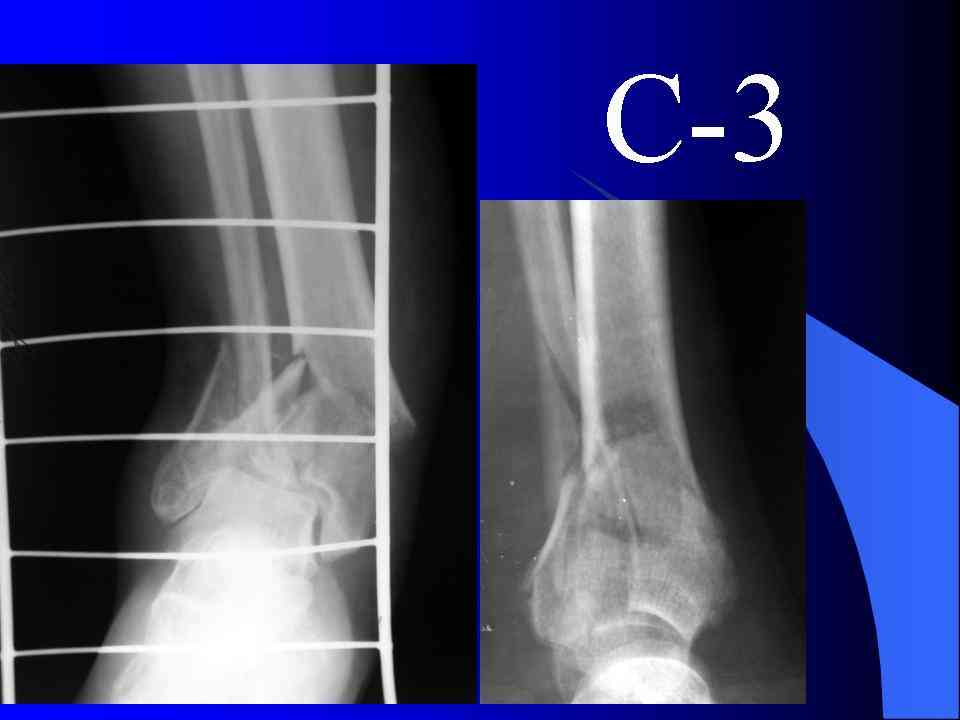

Это типичный перелом пилона, который надп лечить только открыто.Извини те что опоздал к обсуждению, но даже если вы уже оперировали больного по Илизарову это даже лучше.Посылаю картинки.

На рентгенограммах типичный перелом пилона по типу С-3. есть опыт до 100 открытых опреаций у нас в клинике. 20 примерно в год. Принцип один -все внутрисуставные переломы нуждаются в открытой репозиции и внутренней стабильной фиксации. При поступлении КТ не надо, так как получается только нагромождение костей. Истинной картины нет. Главное восстановить длину малоберцовой кости - это ключ к успеху. При поступлении меньше всего надо думать о сосудистых расстройствах, т.к. сама операция и репозиция даже сначала частичная даёт улучшение сосудитых нарушений. Причём очень быстро. Операция в 2этапа. При поступлении доступ позади наружной лодыжки, причём обязательно. После этого репозиция малоберцовой кости и фиксация пластиной 1/3 трубки под винт 3,5. Дренаж и любой аппарат наружной фиксации. Затем после спадения отёка на 5-7-10 день аппрат снимается и дугообразный разрез спереди от медиальной лодыжки 10-12 см. Главной чтобы расстояние между 1 и вторым разрезом было не меньше 7-8 см. Тогда не будет некрозов лоскутов. Таранная кость используется как матрица на неё укладываются отломки и фиксируются пицами. Ренг-контроль. Отломки лежат все отдельно, но ничего не высыпется. При переломах С-3 всегда нужна костная пластика (из крыла). Фиксация пластиной лист клевера простой или LCP. Гипс не нужен. Дренаж до 48 часов. Операция длится 3-4 часа обязательно без жгута. Посылаю примерно такой же случай.

Отправитель: Дрягин В. 04 Январь 2007, 09:00

Послала ещё два снимка, если не пройдут, пошлю ещё. Дрягин. Если есть вопросы, готов ответить.